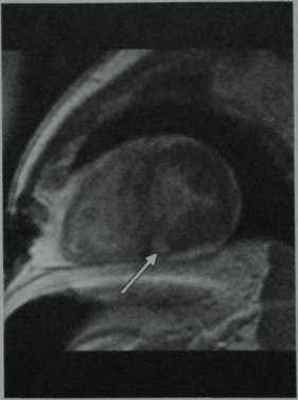

Хроническое отторжение у мужчины 63 лет через 4 года после пересадки сердца. Т2-взвешенная МРТ в режиме TSE с подавлениемсигнала от жировой ткани в проекции по короткойоси сердца демонстрирует выраженную гипертрофию миокарда и увеличение интенсивностисигнала от перегородки в связи с хроническимотторжением.

Тот же пациент. МРТ в режиме IRGE после введения Gd-DTPA демонстрирует диффузное усиление с очагами относительной гиперинтенсивности в нижней частиперегородки (стрелка).